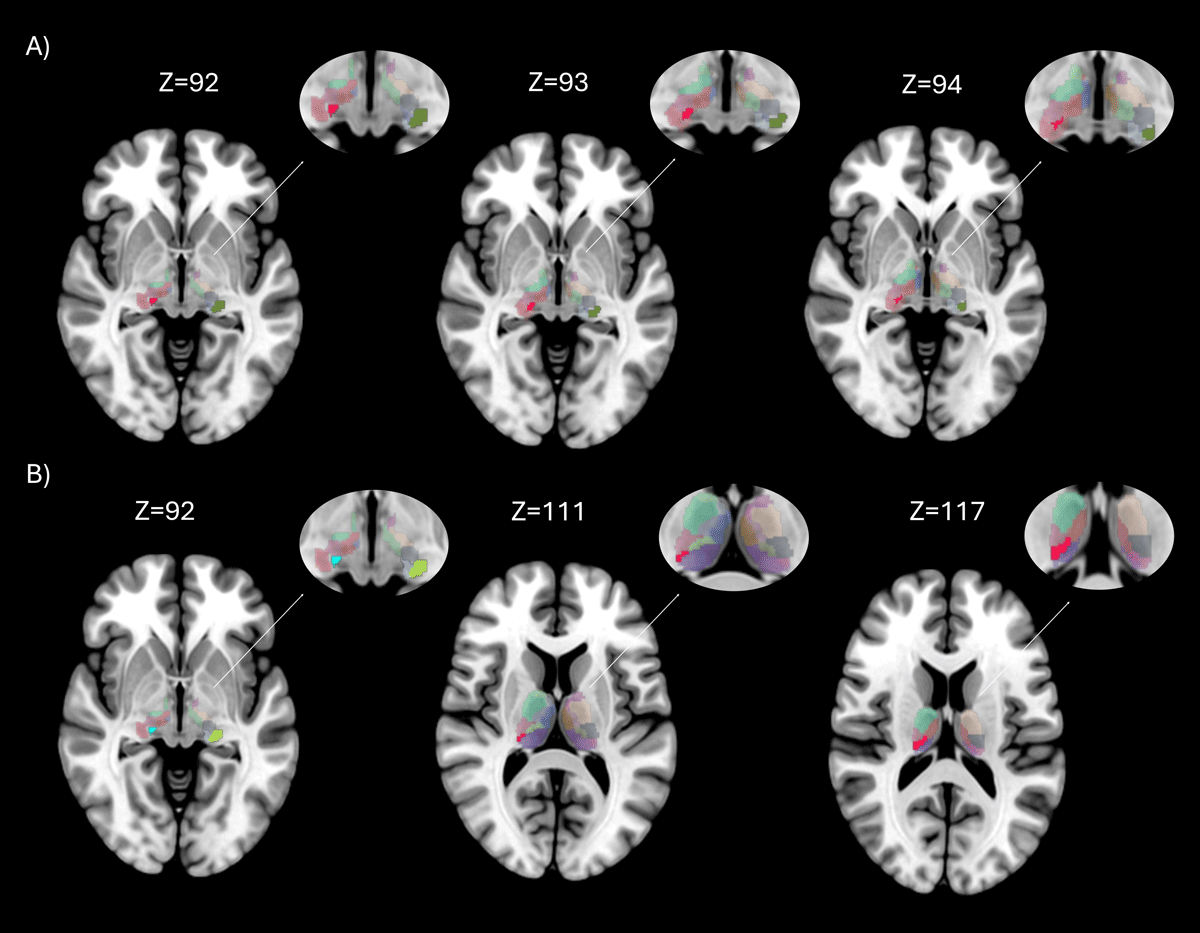

Figure 3

Brain regions with significant differences in nodal properties between groups. Rendering showing regions with significant differences between groups, in axial brain view. The entire thalamus with aal3 atlas is showed in background, while areas with statistically significant differences (p < 0.05 FDR corrected) are highlighted in different colors. Figure 3A shows the differences between Essential Tremor with RBD and Healthy Controls on different axial slices, in red is showed the Right Medial Geniculate Body and in green the Left Lateral Geniculate Body; Figure 3B between Essential Tremor (ET) and Essential Tremor with RBD (ET-RBD) on different axial slices, in light blue is showed the Right Medial Geniculate Body, in green the Left Lateral Geniculate Body, in grey the Right Medial Geniculate body and in red the Pulvinar Inferior.